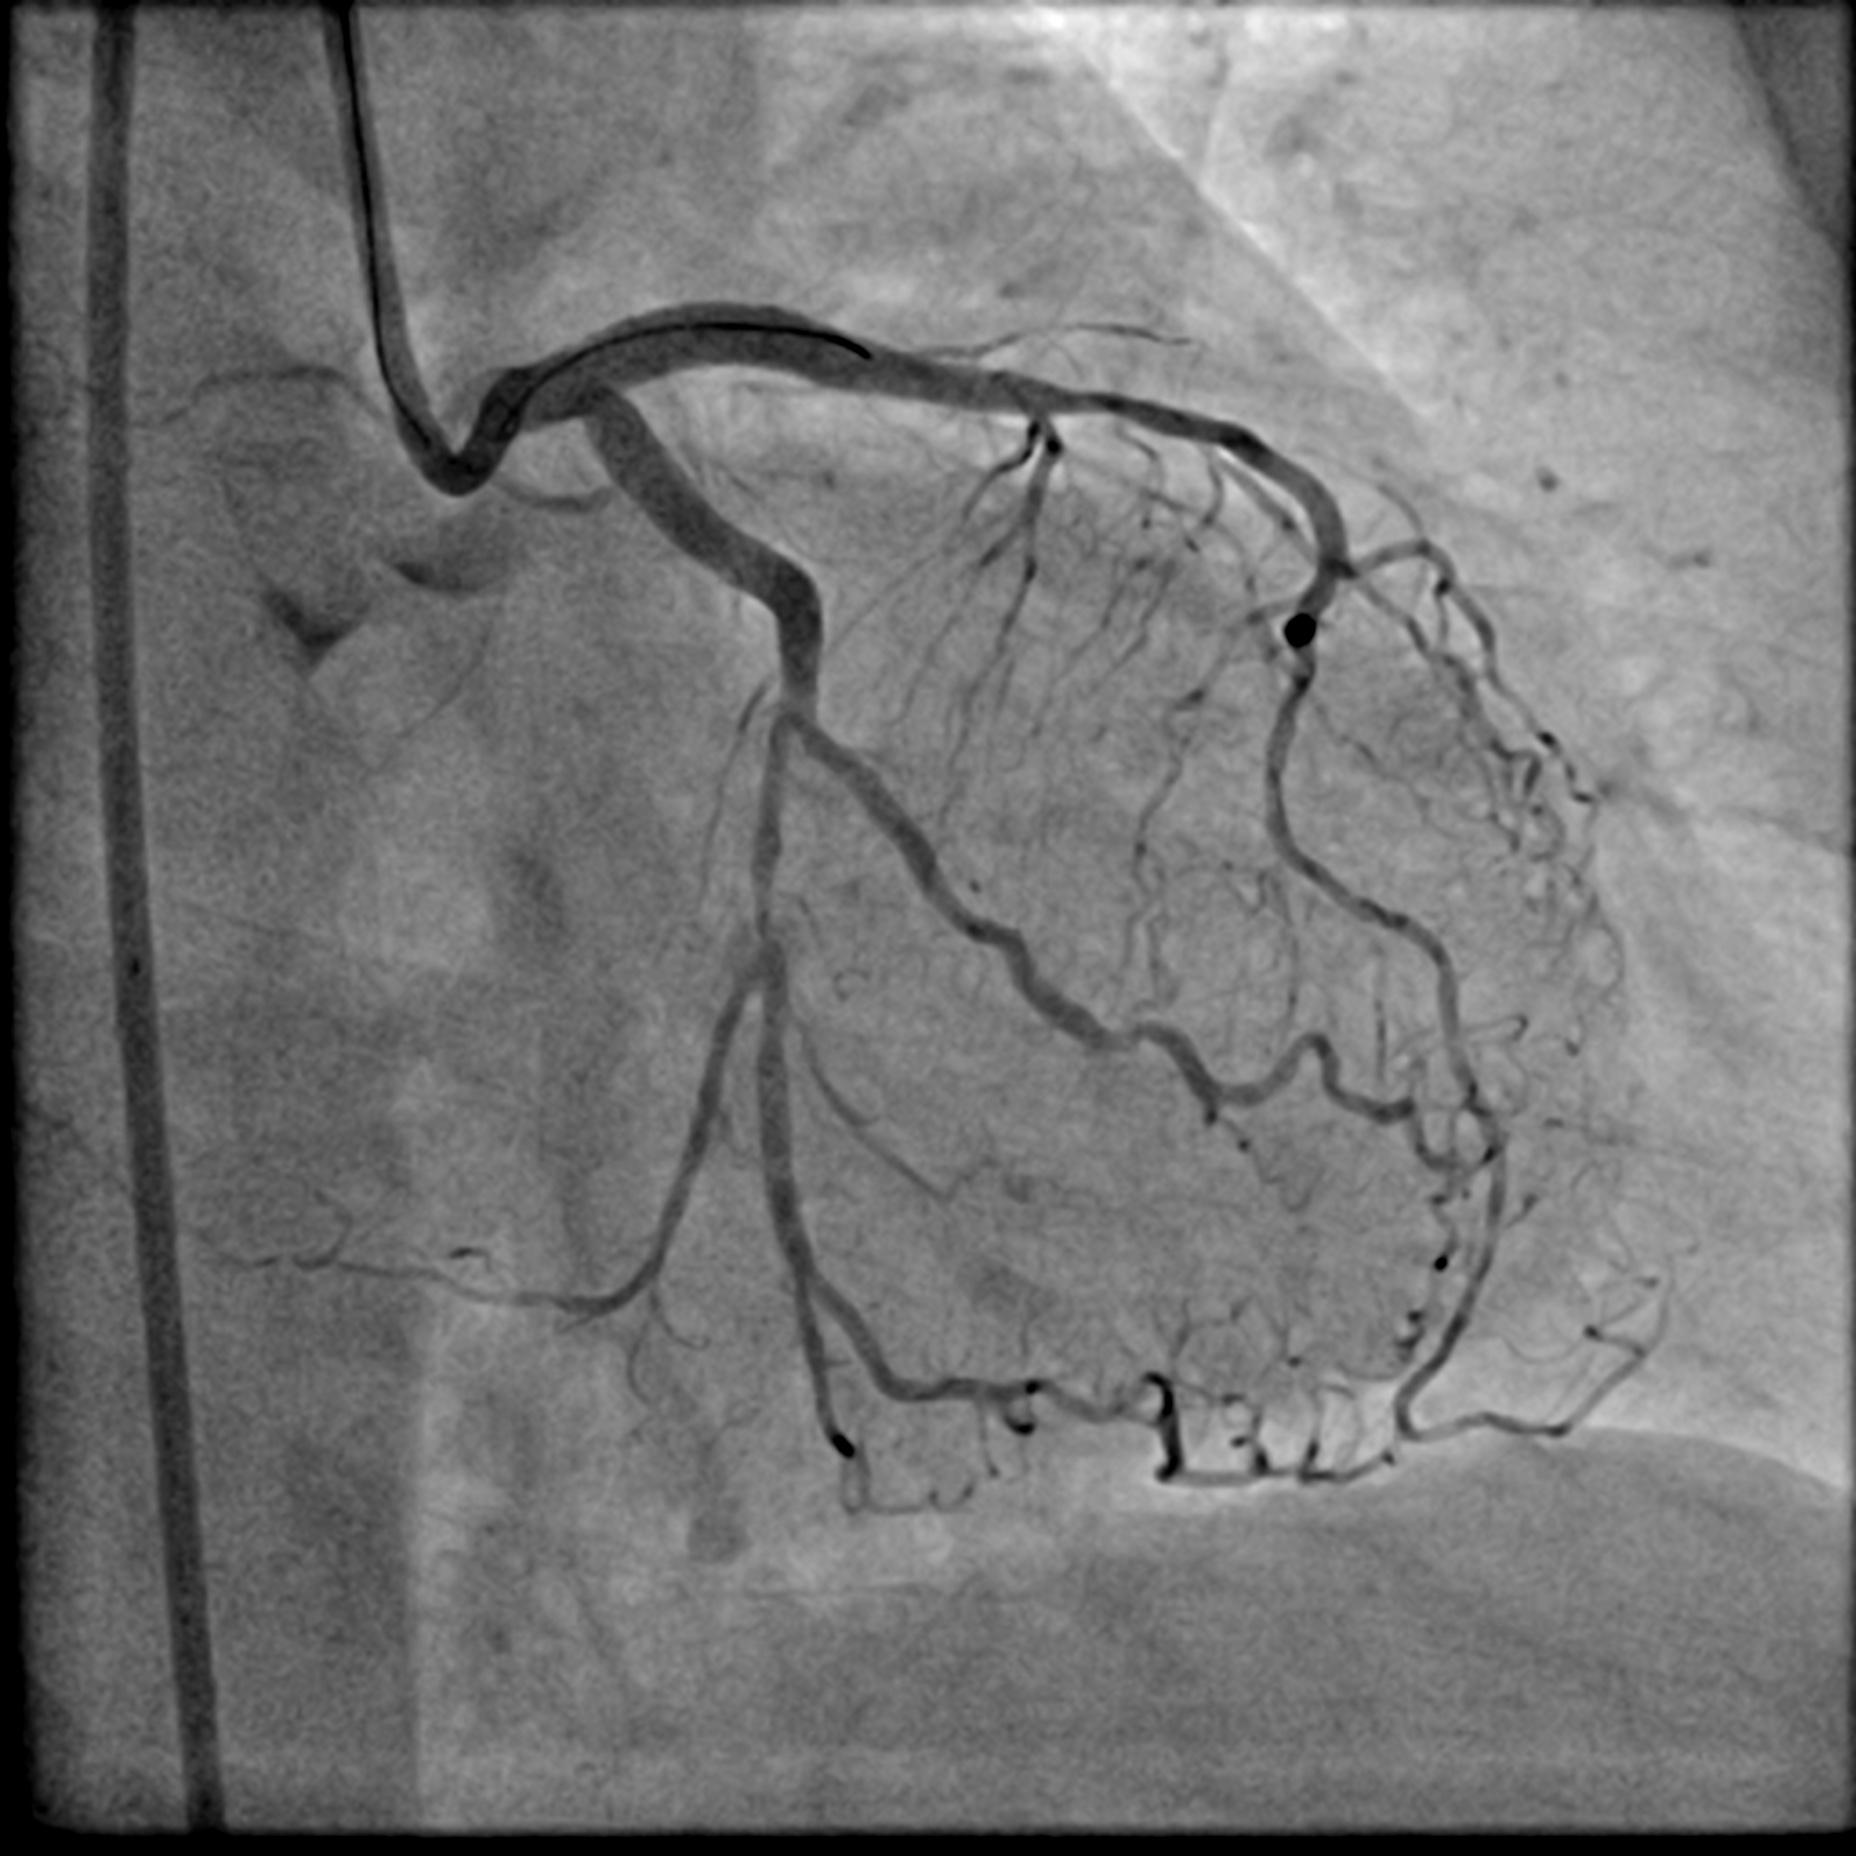

A LMS hybrid therapy was planned. A 7 Fr EBU 3.5 catheter was engaged to the LMS. Two workhorse wires were placed in the distal LAD and LCx. The LAD was pre-dilated with a 3.5 mm cutting balloon without facing significant difficulty. However, pre-dilatation of the LCx with a 3.5 mm cutting balloon was unsatisfactory due to the calcium nodule. This was overcome with lesion preparation using a 3.5 mm Lithix balloon. Adequate lesion preparation was confirmed with repeated angiography and IVUS assessment. The ostial LCx was treated with a 3.5 x 20 mm Drug-Coated Balloon (DCB), while the LMS-LAD segment was stented with a 4.0 x 22 mm Drug-Eluting Stent (DES). Proximal Optimization Technique (POT) was performed using a 4.5 mm NC balloon, and the stent in the LAD segment was post-dilated with a 4.0 mm NC balloon. Repeated angiography revealed a Type B dissection with a narrowed lumen in the LCx, necessitating stenting. The LCx was re-wired using a dual-lumen catheter from the inner frame of the LMS stent. The stent strut was opened with a 2.0 mm balloon and a 3.5 mm NC balloon. T-stenting of the ostial LCx was performed with a 3.0 x 26 mm DES, utilizing a balloon catheter in the LAD wire as a marker. The LCx stent was first post-dilated with a 3.5 mm NC balloon. Subsequently, the Kissing Balloon Technique (KBT) was performed with a 4.0 mm NC balloon in the LAD and a 3.5 mm NC balloon in the LCx. Finally, repeated POT was completed with a 4.5 mm NC balloon in the LMS.

LCA final AP cran.mp4

LCA final AP Caud.mp4

Case Summary